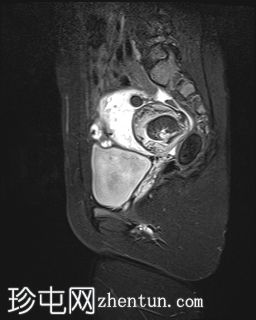

MRI扫描

冠状扫描

T1

右侧附件区可见较大囊性肿块,内含脂肪和液体,大小约为86毫米 x 60毫米。右侧血管蒂扭转,呈漩涡征。右侧卵巢可见增大充血的卵泡,为囊性肿块病变。左侧卵巢正常。